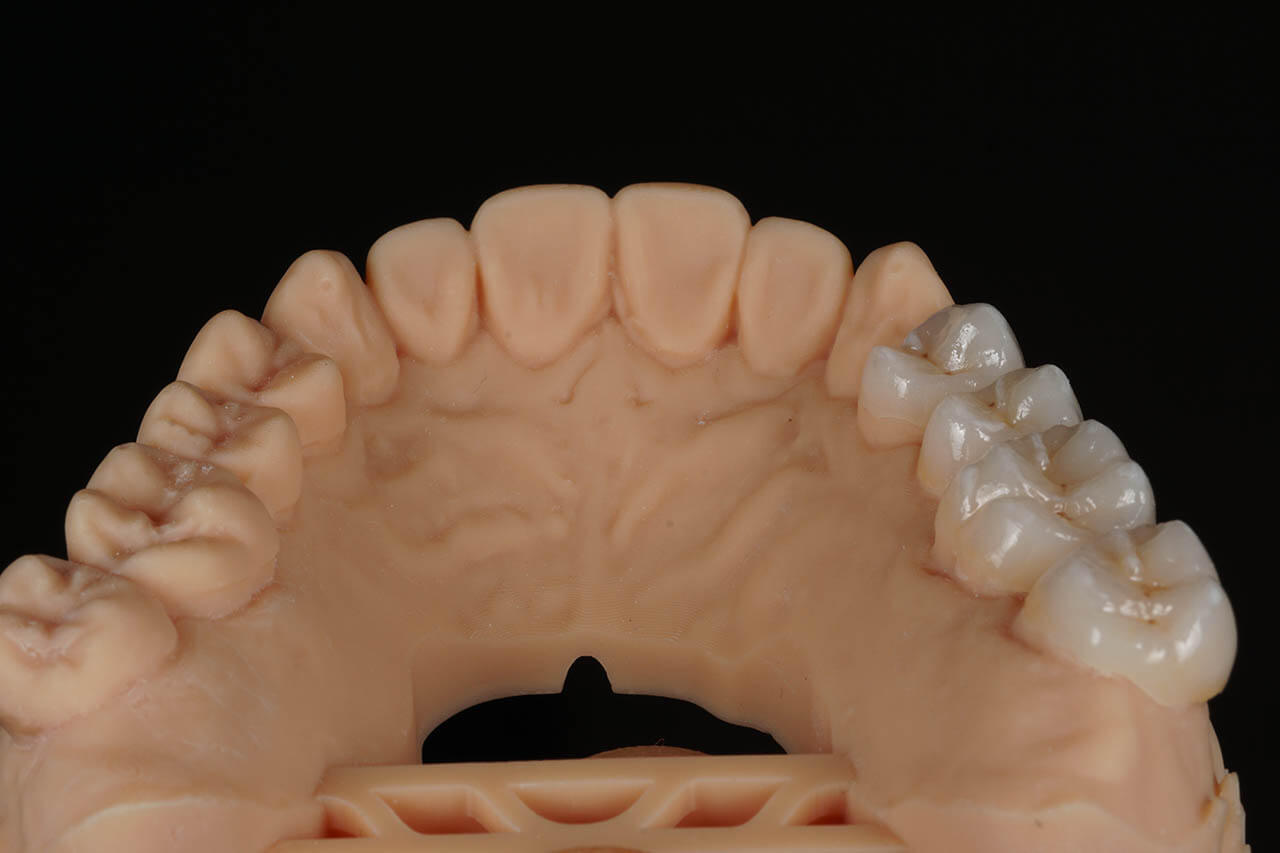

Dental prosthetics deals with filling gaps in the dentition and reconstructing damaged teeth. It is a good choice for anyone who in the past did not properly care for their teeth and as a result could not maintain their natural dentition or lost teeth due to illness or an unfortunate event. A properly chosen partial or full denture allows for the recovery of an aesthetic smile, good well-being, and self-confidence. Prosthetics at the Z Wieży clinic in Władysławowo offers you a wide range of modern prosthetic solutions, from which everyone can choose something tailored to their needs and expectations regarding the final result. Our experienced, highly qualified doctors are ready to provide assistance and good advice. To ensure the highest quality and aesthetics of restorations, we have for years cooperated with a renowned prosthetic laboratory.

Types of prosthetic restorations used at the Z Wieży clinic:

• Porcelain and all-ceramic prosthetic crowns;

• Acrylic and zirconia crowns;

• Dental bridges and dentures.

Our prosthetic work